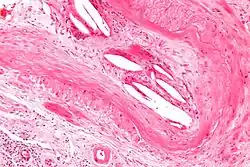

| Micrograph showing a cholesterol embolus in a medium sized artery of the kidney. Kidney biopsy. H&E stain. | |

The microscopic examination of tissue (histology) gives the definitive diagnosis. The diagnostic histopathologic finding is intravascular cholesterol crystals, which are seen as cholesterol clefts in routinely processed tissue (embedded in paraffin wax).[7] The cholesterol crystals may be associated with macrophages, including giant cells, and eosinophils.

The sensitivity of small core biopsies is modest, due to sampling error, as the process is often patchy. Affected organs show the characteristic histologic changes in 50-75% of the clinically diagnosed cases.[3][5] Non-specific tissue findings suggestive of a cholesterol embolization include ischemic changes, necrosis and unstable-appearing complex atherosclerotic plaques (that are cholesterol-laden and have a thin fibrous cap). While biopsy findings may not be diagnostic, they have significant value, as they help exclude alternate diagnoses, e.g. vasculitis, that often cannot be made confidently based on clinical criteria.